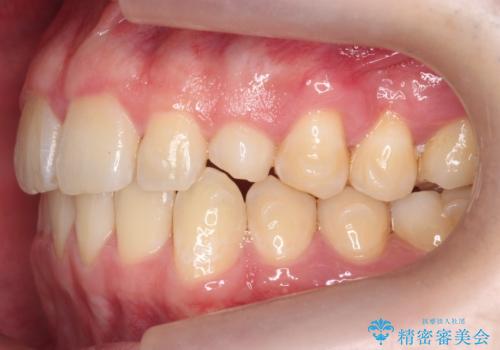

前歯のすき間、犬歯の異所萌出 乳歯を抜かずに矯正

- 前歯のすきまと八重歯を主訴に来院。

左上の乳犬歯が残っており、その下から生えてくるはずの犬歯(永久歯)が左上小臼歯部に萌出していました。

左上の乳犬歯は根もしっかりしていたため、

を提案し、➀を選択されました。

将来的にインプラントは希望されないとのことだったため、乳歯の部分は隙間を開けてインプラントを入れる用のすき間を確保するということは特に行いませんでした。

乳歯をそのまま並べたため、上顎の左右の犬歯の幅は非対称になっています。